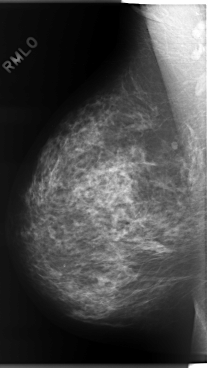

C_0071_1.RIGHT_MLO

ics_version 1.0

filename C-0071-1

DATE_OF_STUDY 9 11 1994

PATIENT_AGE 48

FILM_TYPE REGULAR

DENSITY 3

DATE_DIGITIZED 30 10 1997

DIGITIZER LUMISYS LASER

RIGHT_MLO LINES 5880 PIXELS_PER_LINE 3320 BITS_PER_PIXEL 12 RESOLUTION 50 NON_OVERLAY